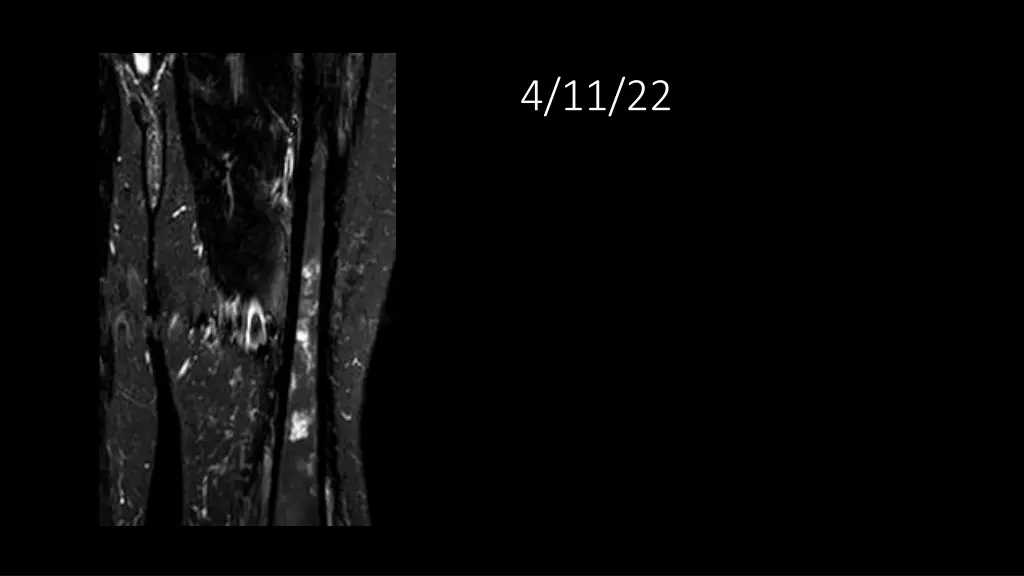

62-year-old shows post-surgery progress from 11/4/2020 to 4/11/22

Explore the journey of a 62-year-old individual post-UPS resection on 11/4/2020, through a series of dated images leading up to 4/11/22. Witness the transformation and recovery process in these visual updates reflecting the progression over time.